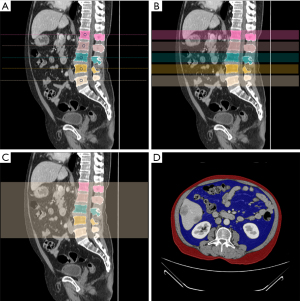

SFV measured by CT

The basic principle of CT measurement of SFV is to distinguish the density of different tissues by the attenuation coefficient of X-rays, and to segment and quantify adipose tissue using computer image reconstruction technology. Specifically, when CT scanning utilizes X-rays to penetrate the human body, different tissues have different absorptions of X-rays, resulting in images with different gray values. Adipose tissue can be separated from other tissues by setting a range of CT values, such as subcutaneous fat, which is usually −190 to −30 Hounsfield units (HU). Abdominal adipose tissue was manually labeled by two radiologists with years of experience in tumor imaging using ITK-SNAP software. Subcutaneous adipose tissue (SAT) and visceral adipose tissue (VAT) were labeled. After the initial labeling was completed, the labeling results were reviewed by a third senior radiologist to ensure the accuracy and consistency of the labeling. After obtaining the information of the lumbar spine level, we performed a detailed analysis of the horizontal plane of each vertebral body (L1 to L5) and measured the volume of abdominal adipose tissue (including SAT and VAT) at that level. At the same time, we further focused on the level of the center of mass of each vertebral body, that is, the plane of the center of mass of L1 to L5 vertebral bodies was determined by the geometric center method, and the abdominal fat mass at this level was calculated. SAT and VAT volumes were calculated separately for each vertebra (L1 through L5) at the level of the center of gravity (Figure 1).